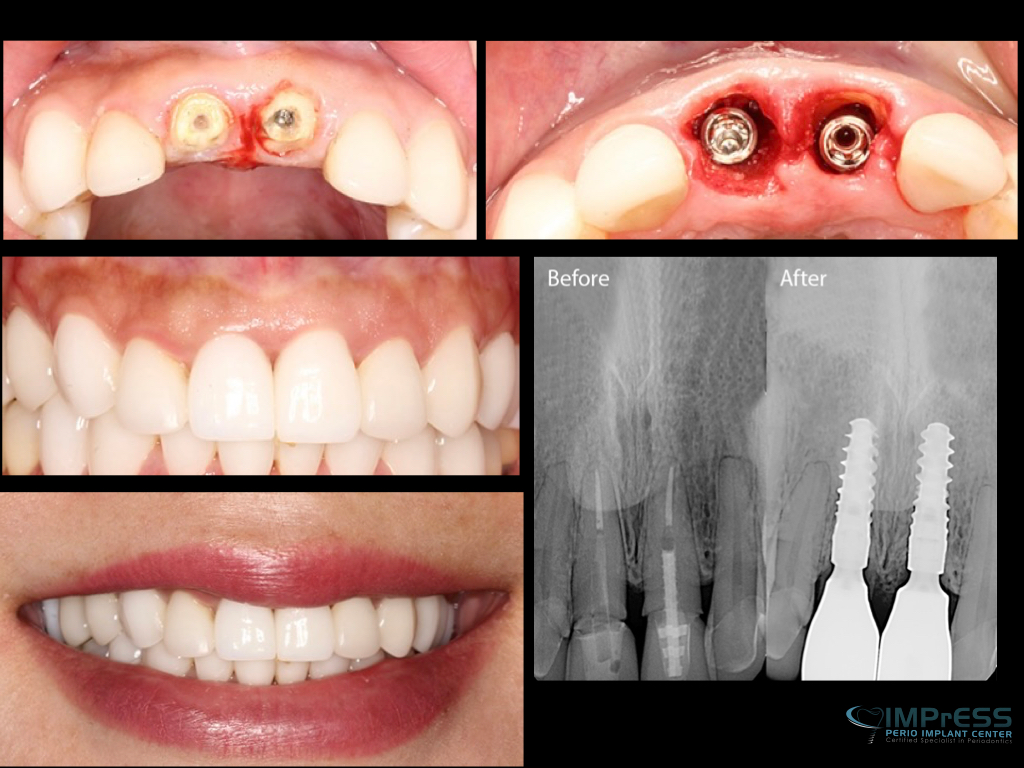

IMPrESS Perio Immediate upper front implants with partial extraction therapy, guided surgery and provisional and final crowns

Front Teeth Dental Implants in Vancouver

IMPrESS Perio Immediate upper front implants with partial extraction therapy, guided surgery and provisional crowns